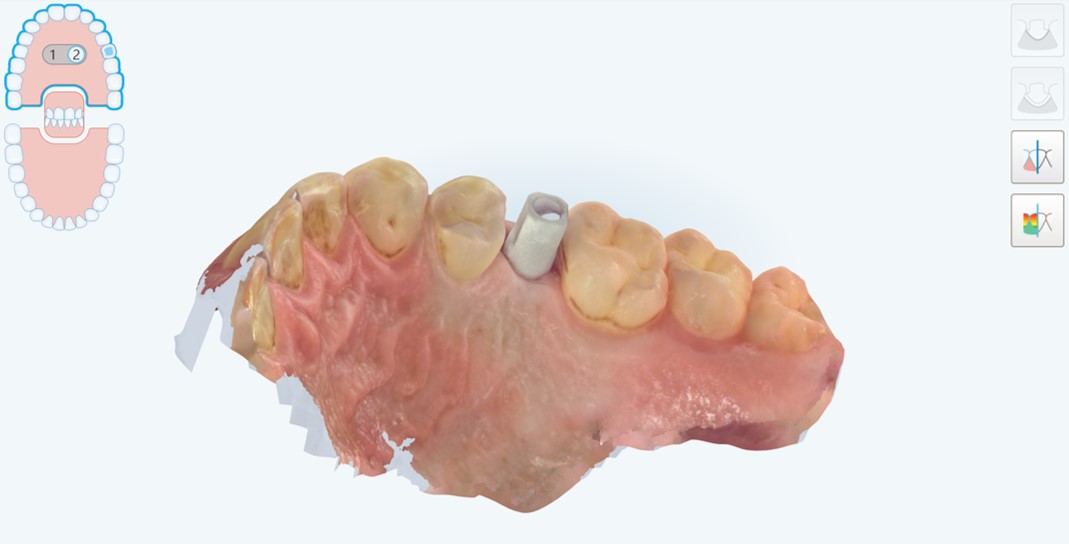

Passato un periodo di tre mesi, necessario al completamento dell’osteointegrazione, si procedeva con la scopertura dell’impianto (Fig. 6) e la cattura della posizione dello stesso attraverso impronta ottica con potente scanner intraorale (Itero Element 5D Plus®, Align Technologies, San Josè, USA). Lo scanbody era one-piece, prodotto in titanio poroso (TQM®, Gioia del Colle, Bari, Italia) (Fig. 7,8,9,10).

impronta ottica con potente scanner intraorale

Fig. 6. A distanza di 3 mesi, è possibile procedere con l’impronta ottica con potente scanner intraorale (Itero Element Plus 5D®, Align Technologies, San Josè, CA, USA). Visione occlusale della vite di guarigione.

Impronta ottica del modello master con il collare mucoso esposto

Fig. 7. Impronta ottica del modello master con il collare mucoso esposto, dopo rimozione dell’healing abutment, e del modello antagonista in masticazione.